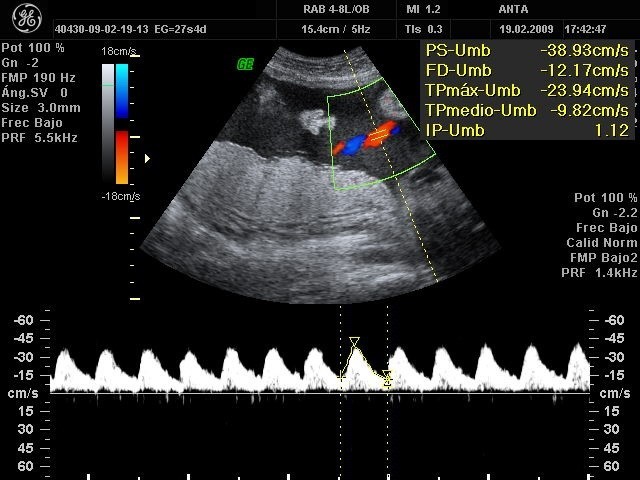

La ecografía o ecosonografía es un procedimiento de imagenología que emplea los ecos de una emisión de ultrasonidos dirigida sobre un cuerpo u objeto como fuente de datos para formar una imagen de los órganos o masas internas con fines de diagnóstico. Un pequeño instrumento «similar a un micrófono» llamado transductor emite ondas de ultrasonidos. Estas ondas sonoras de alta frecuencia se transmiten hacia el área del cuerpo bajo estudio, y se recibe su eco. El transductor recoge el eco de las ondas sonoras y una computadora convierte este eco en una imagen que aparece en la pantalla.